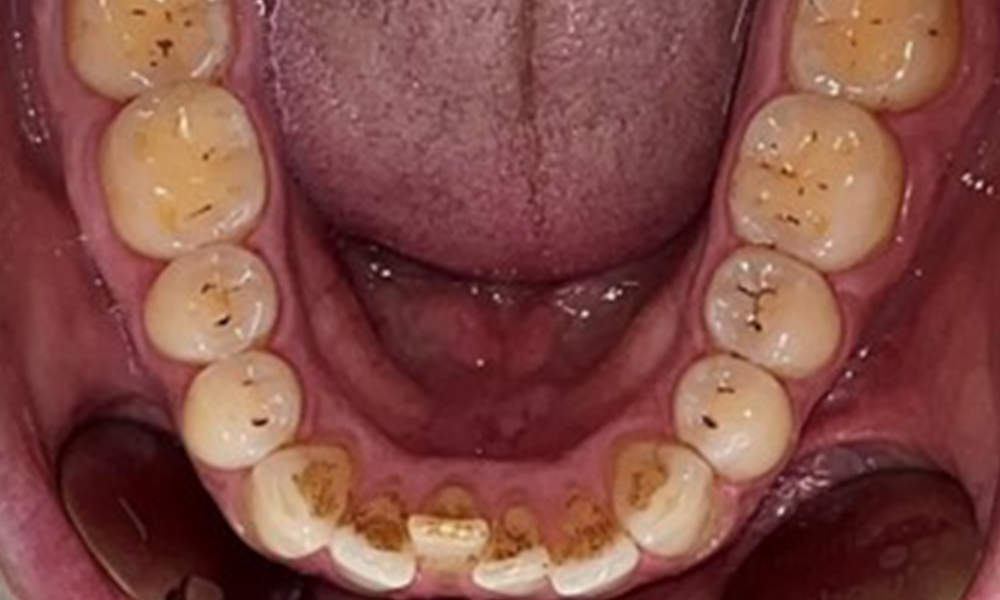

Occlusal view of the mandible.

Fig. 4: Occlusal view of the mandible, © Dr R. Krapf

There were no pathological extraoral findings. During intraoral examination, inspection of the frontal view revealed brownish discolouration near the keratinised gingiva and at the transition to the moveable mucosa (Fig. 2), which could be attributed to nicotine consumption. Whitish mucosal lesions were observed on the palate, particularly near the maxillary molar palatal surfaces, indicating increased keratinisation and can also be attributed to nicotine consumption. The tongue was covered with a removable white and brownish coating.

The patient has full dentition with a total of 28 teeth. There were noteworthy erosions and attritions. (Fig. 4, Fig. 5). Due to bruxism, the patient has been wearing a splint with an adjusted bite block at night for many years. The erosions were caused by long-term consumption of isotonic beverages. No periodontal bone loss or active caries were observed.